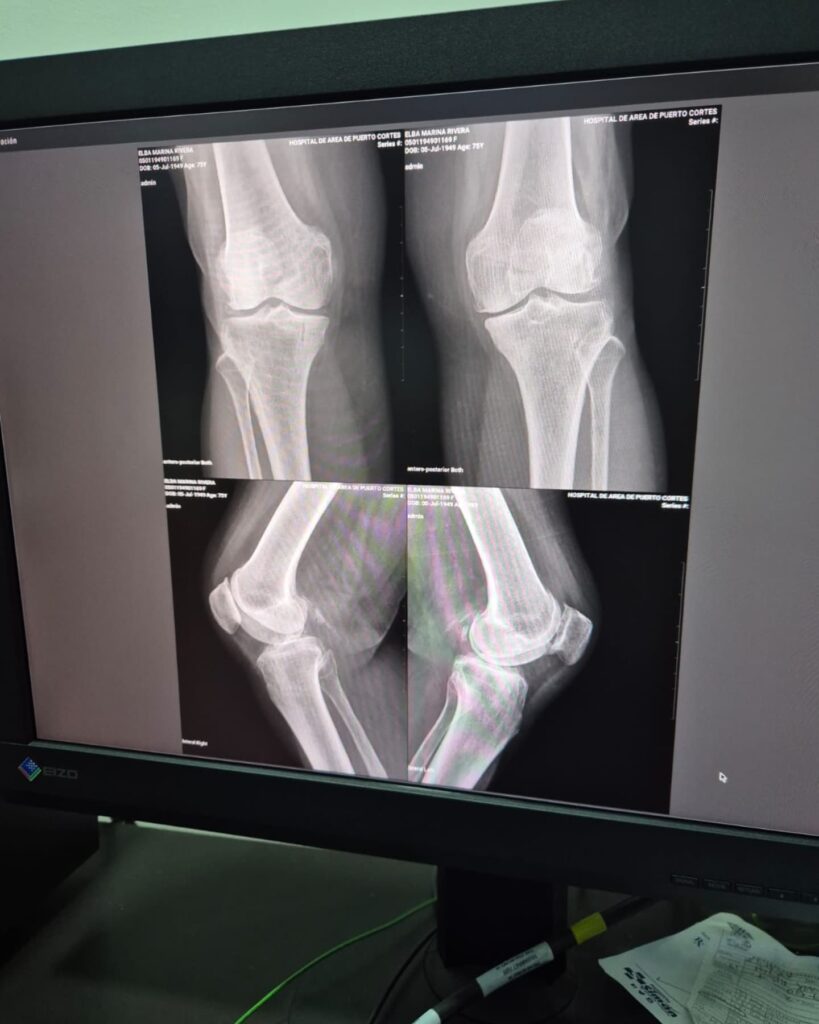

El nuevo equipo permitirá realizar estudios radiográficos con mayor precisión y eficiencia, reduciendo tiempos de espera y facilitando diagnósticos oportunos para pacientes que requieren evaluación médica. Con esta modernización tecnológica, se estima un beneficio directo para más de 142 mil habitantes de la zona de influencia del centro hospitalario.

Personal de salud destacó que contar con tecnología actualizada en radiología es clave para detectar a tiempo diversas condiciones médicas y tomar decisiones clínicas más acertadas, lo que impacta directamente en la recuperación y bienestar de los pacientes.